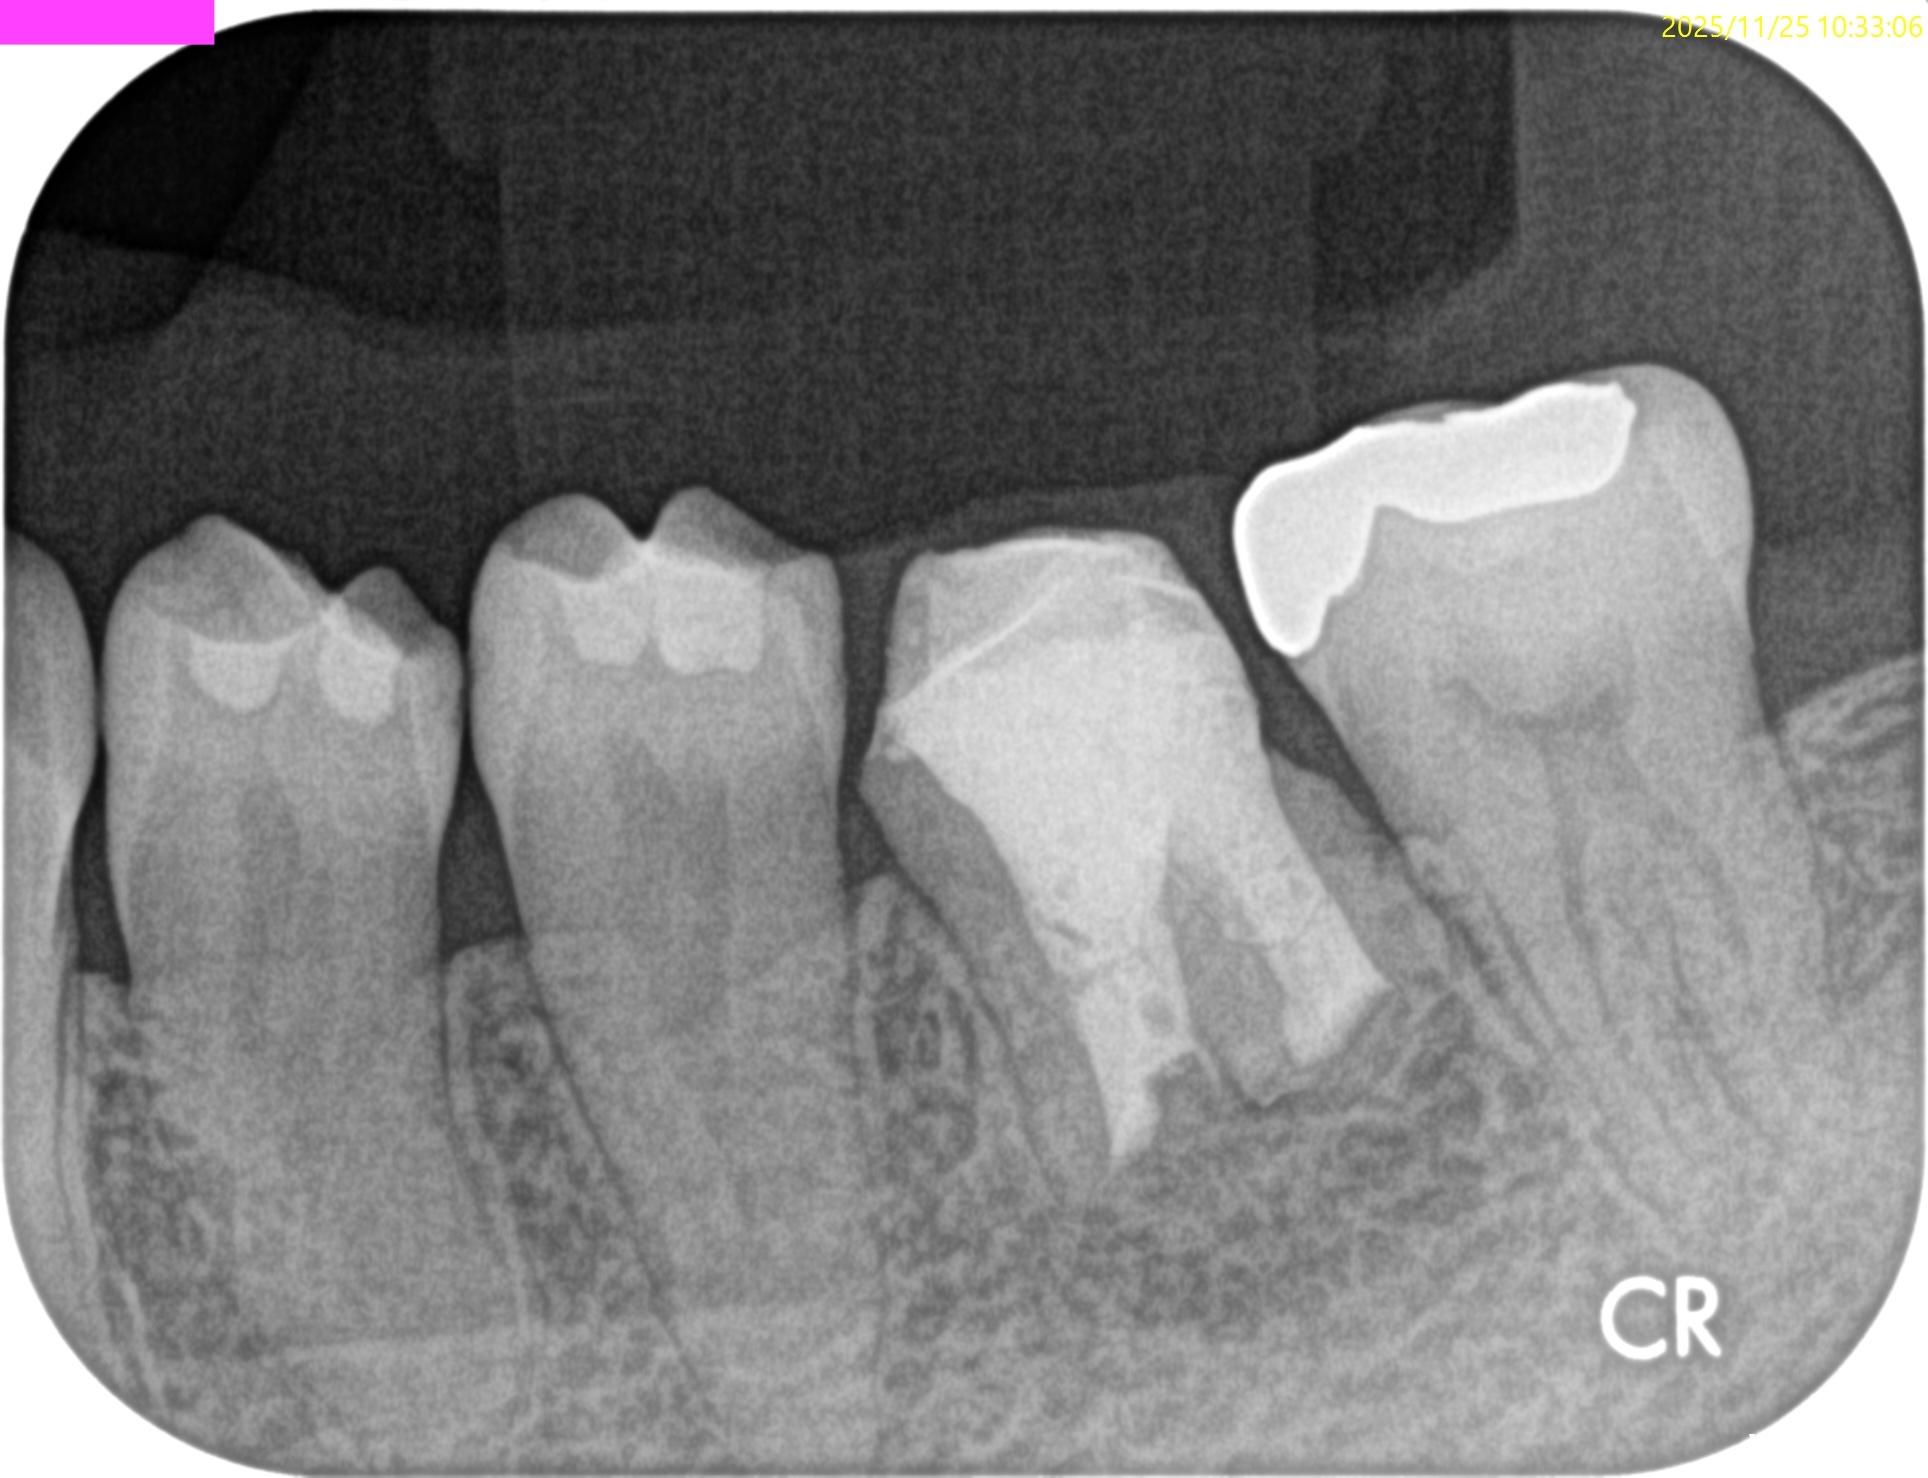

#19 M,D Apicoectomy 1yr recall(2025.11.25)

Sinus tractは

B,Lともに消失した。

M

D

術前・術直後と比較した。

90%がた治癒していると言えるだろう。

かかりつけ医の先生には最終補綴を依頼した。

Mがhealing(治癒途中)というところなのでその次の年も経過観察を患者さんには依頼させていただいた。